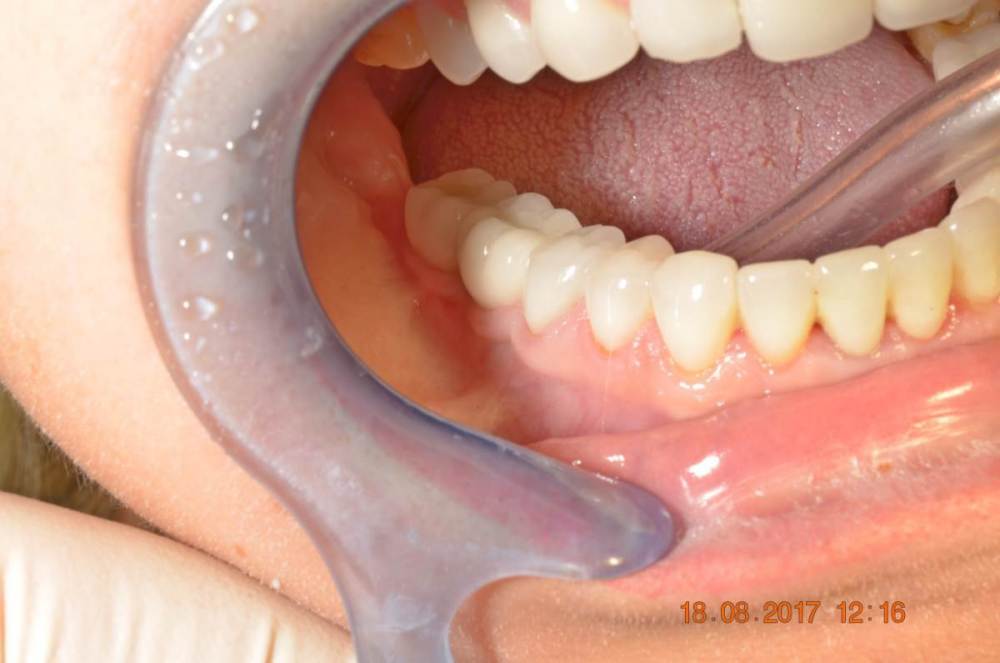

Большой Зеленый Опубликовано 15 августа, 2023 Поделиться Опубликовано 15 августа, 2023 Винтовая фиксация . 8 лет наблюдений .Полет нормальный. Немного прокрасились пломбы в шахтах. Пациентка довольна и счастлива. Привела уже вагон беззубых друзей и родственников. P/S. Система имплантов Ирис...:) 1 Ссылка на комментарий